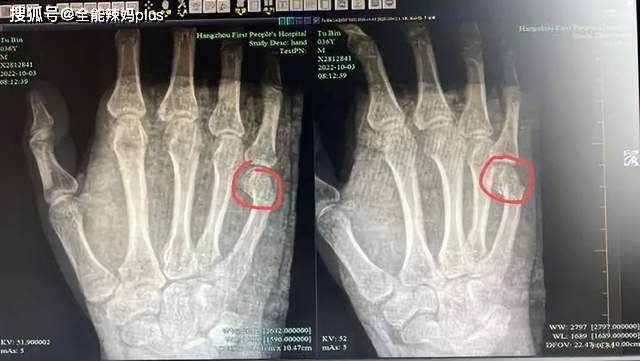

近来,我看到了一些家长辅导作业的视频,真让人感到震惊。一位母亲因为辅导作业,竟然让自己的乳腺结节和甲状腺结节加重;还有家长因愤怒而拍桌子,结果手掌骨折,甚至有家长在辅导孩子作业时因为压力过大而猝死!每当看到孩子们在父母怒吼下吓得浑身发抖、不敢言语,甚至哭泣时,我心里不禁感到沉重。